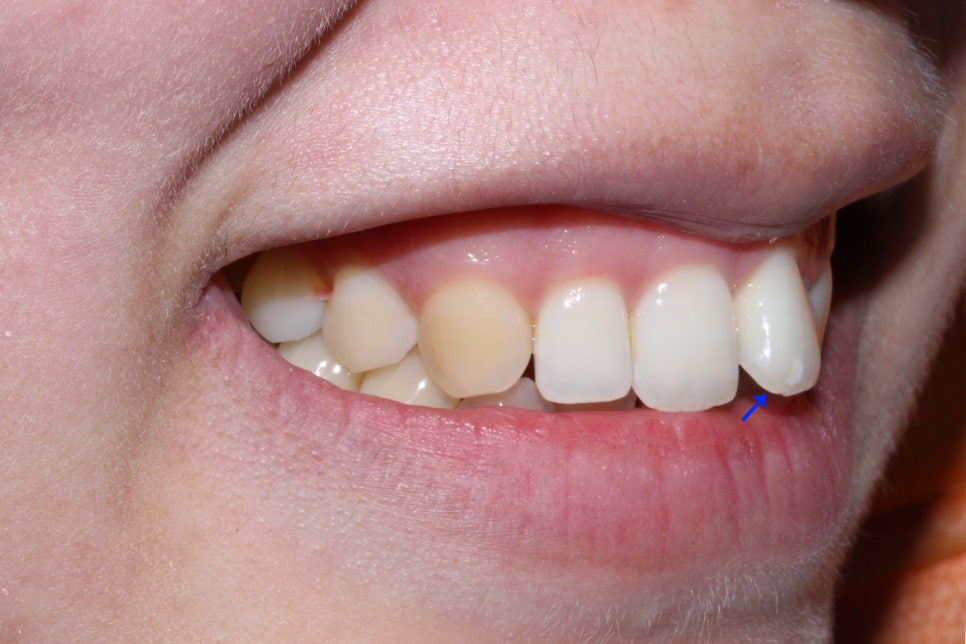

뻐드렁니 교정 전 중절치의 돌출 상태를 보시면

위처럼 중절치가 맹출된 각도가 지나치게

튀어나온 것을 확인할 수 있습니다.

왜소치 외에도 상악 왼쪽 중절치의 표면에

흰 반점이 있는 반상치 증상이 나타나기 때문에

이 부분은 추후 치아색과 비슷한 resin으로

보완하여야 하는데요, 이러한 반상치 증상이

부분적으로 나타나는 것이 아닌 치아 표면에

전체적으로 발생하여 resin 치료가 불가능한 경우

무삭제 라미네이트 '세라필름'을 부착하여

치아의 표면을 매끈하고 균일하게 보완할 수 있습니다.